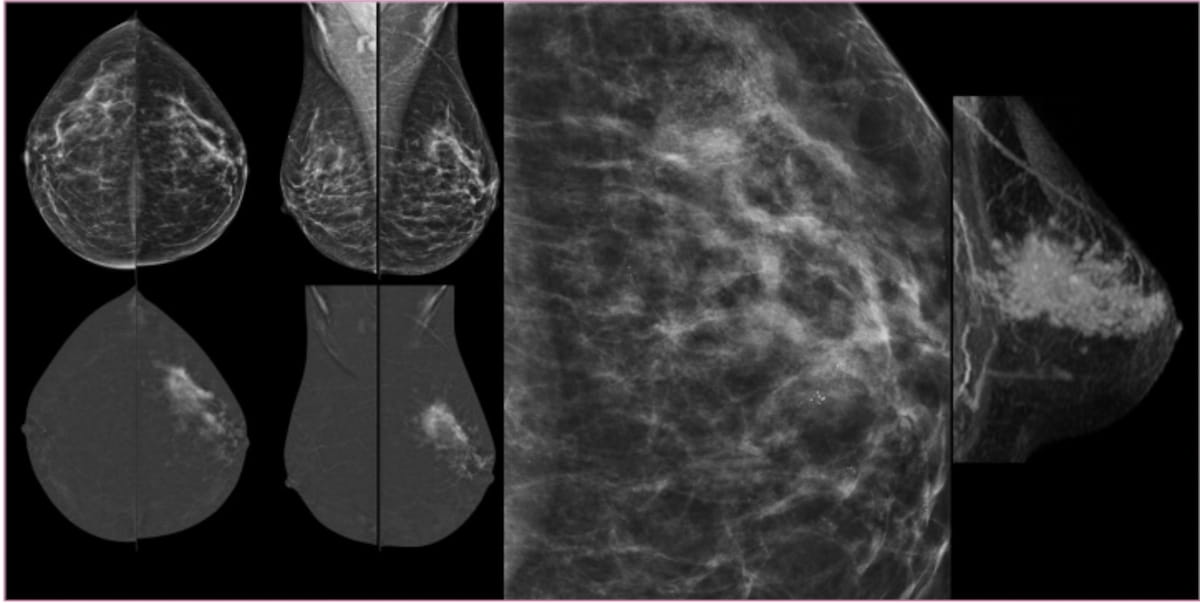

For women with dense breasts, abbreviated breast MRI and digital breast tomosynthesis (DBT) both offered greater than 98 percent sensitivity rates and greater than 94 percent negative predictive values (NPVs) for breast cancer detection, according to newly published research.

Contrast-enhanced mammography had a 98 percent sensitivity rate for diagnosing invasive lobular carcinoma and provided high conspicuity for 82 percent of detected lesions, according to research presented at the recent Radiological Society of North America (RSNA) conference.